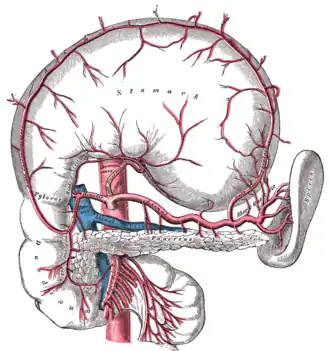

The celiac artery and its branches. | |

Branches of the celiac artery. The gastroduodenal artery appears on the left part of the figure and overlays/is anterior to the portal vein. The stomach is raised and inverted - compare with celiac artery branches - stomach in situ. | |